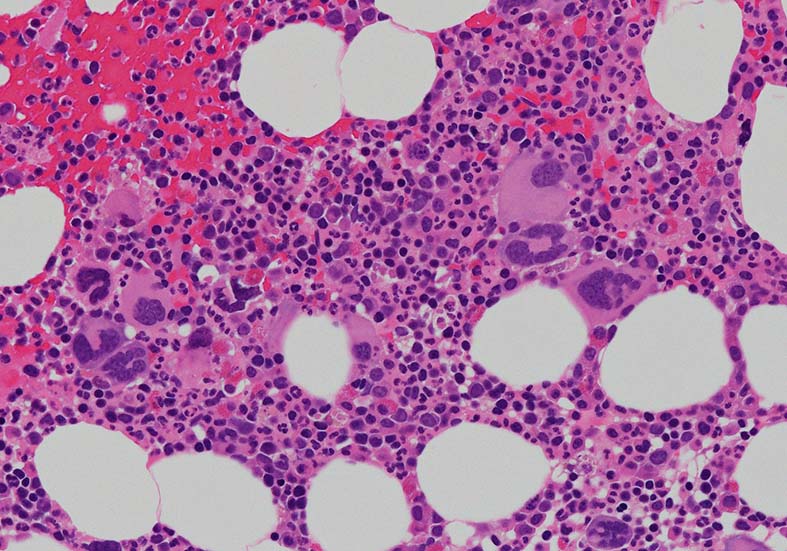

骨髄組織所見

cellularity60-70%ほどの過形成髄. ETは通常, 正形成髄から軽度の過形成髄, まれに低形成髄のこともある. 本例は軽度過形成傾向なcellularity. 巨核球数増加が目立つほか, stag-horn, cloud-likeといわれる核をもつ大型巨核球が認められる他, 小型で若い巨核球も増加している. ETでは, 連続する巨核球分化が認められる. 顆粒球系細胞増多が認められる.

Mgkの凝集所見があるが, 5-6個の緩やかな凝集で, loose clusterと呼ばれる. (Dens cluster:9個以上[数は厳密]の密なcohesiveな増殖は線維化がない場合, prefibrotic myelofibrosisの重要な所見になる)